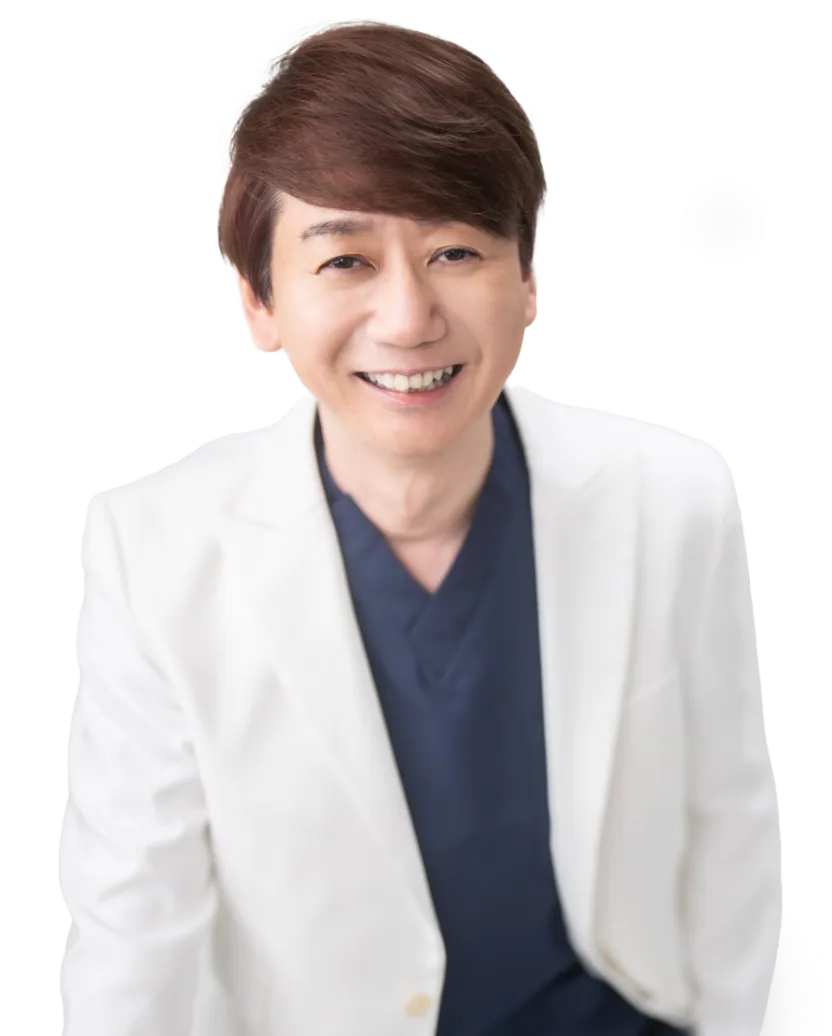

Message

入れ歯治療というと、「失った歯を補う」イメージが先行しがちですが、本来は毎日の食事をおいしく楽しみ、明るく話し、思いきり笑うための“生活の質”を向上させる大切な治療です。

そのため当院では、患者さま一人ひとりの生活スタイルやご希望を、しっかりとお伺いするカウンセリングを大切にしています。

入れ歯の作り方や素材にもいろいろな選択肢があり、どのタイプがご自身にしっくりくるのかは、実際に試してみないとわからない部分も多いものです。私達はそのサポートを全力で行い、なるべく「装着感のよさ」を大切に、納得のいく入れ歯を一緒に探していきたいと考えています。

資格・所属

- ・NPO法人日本歯科予防協会理事

- ・ブローネマルクインプラント認定

- ・AQBインプラント認定

- ・ITIインプラント認定

- ・SARGONインプラント認定

- ・POIインプラント認定

- ・ザイブインプラント認定

- ・ドライマウス認定医

- ・審美歯科学会認証

- ・マウスピース矯正認定

- ・日本ドライマウス学会会員

- ・日本抗加齢歯会会員

- ・インプラント学会 所属

- ・医療情報技師認定証